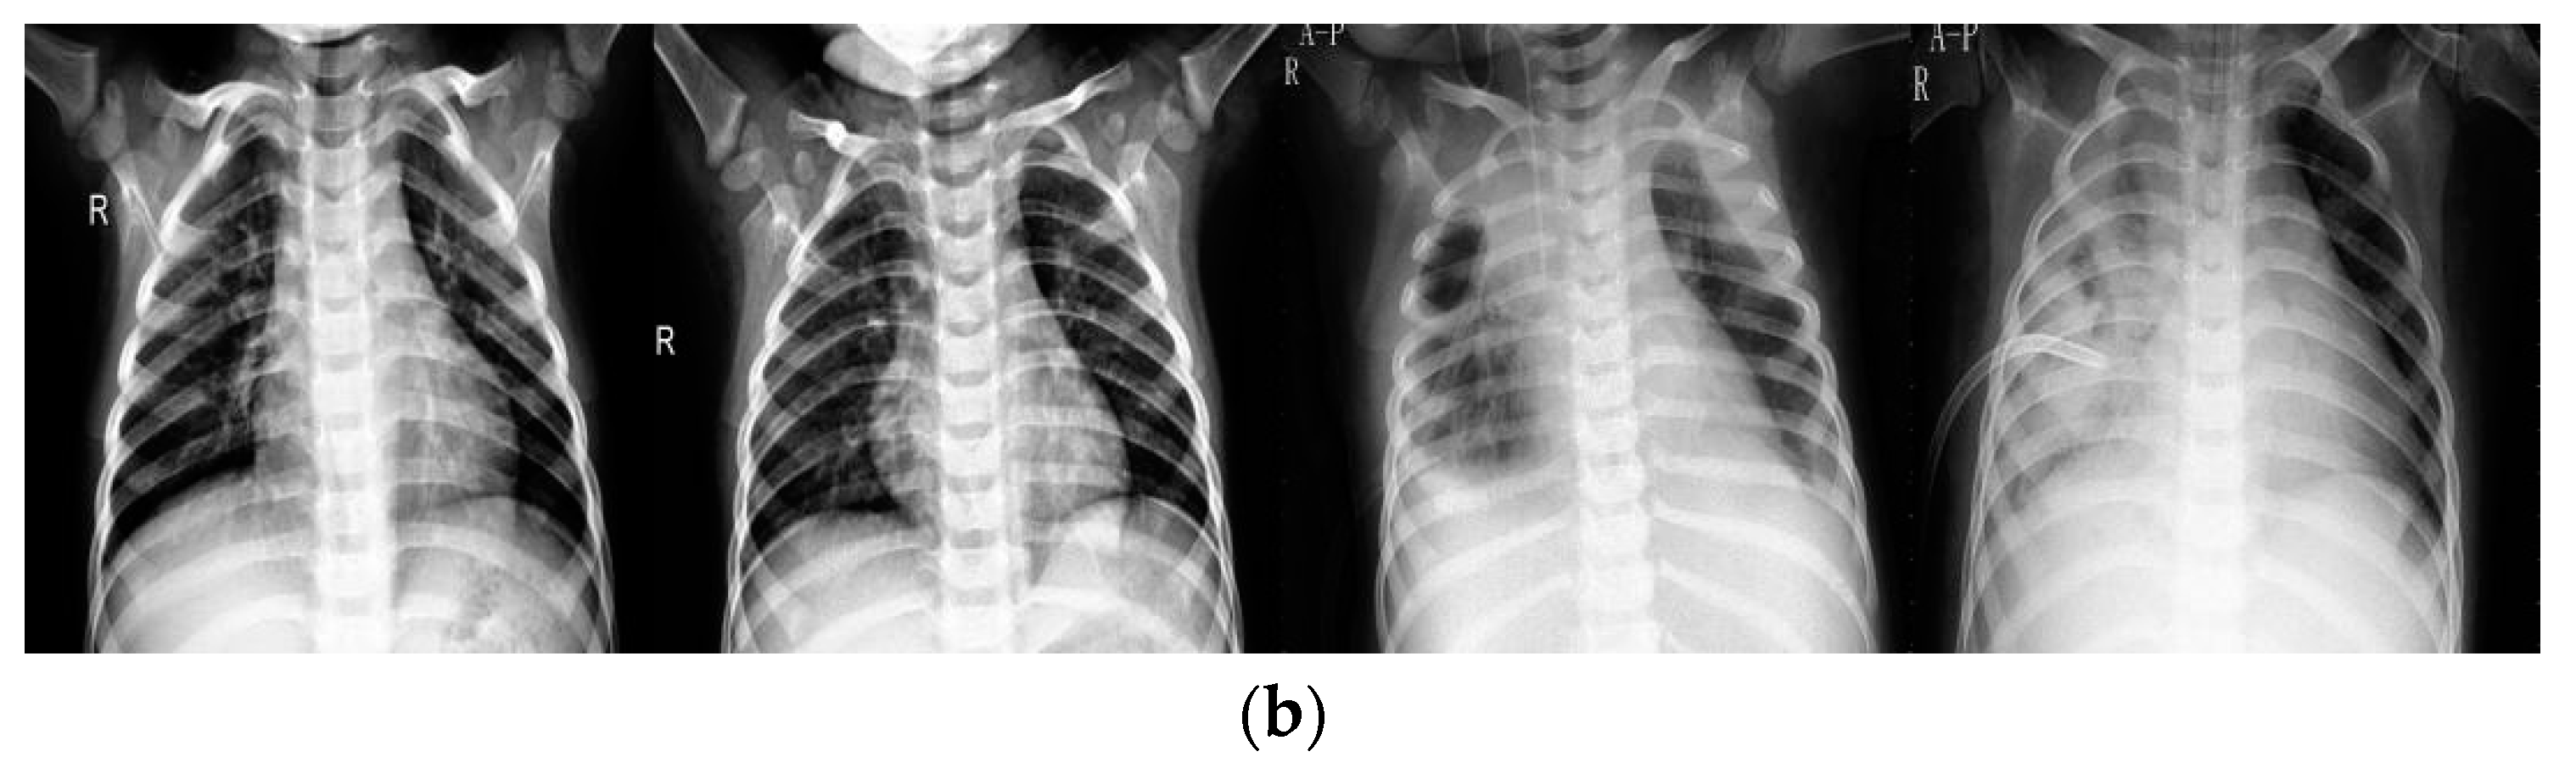

4.1. Data

4.2.1. Data Pre-Processing